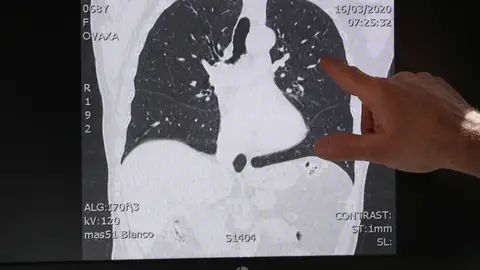

María Luisa Hurtado habla con el doctor José Manuel Quesada del Instituto Maimónides de Investigación Biomédica de Córdoba, IMIBIC, sobre el ensayo con Calcifediol en pacientes con coronavirus.